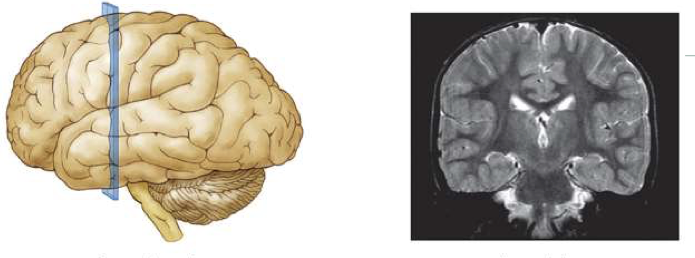

What is the difference between anatomical directions and brain planes (slices)?

Anatomical directions tell us where something is in the brain (e.g., front, back, top).

Brain planes (slices) show how the brain is cut for viewing (like in an MRI).

🧠 Directions = Location

✂ Planes = How we look inside

What is this brain plane called?

Coronal Section

A cut from side to side showing the brain from the front.

like looking at a face

What is this brain plane called?

horizontal section

A top-down cut showing the brain from above

like slicing a hamburger bun

What is this brain plane called?

Sagittal Section

A cut from front to back in the middle, showing the brain from the side

like a profile view